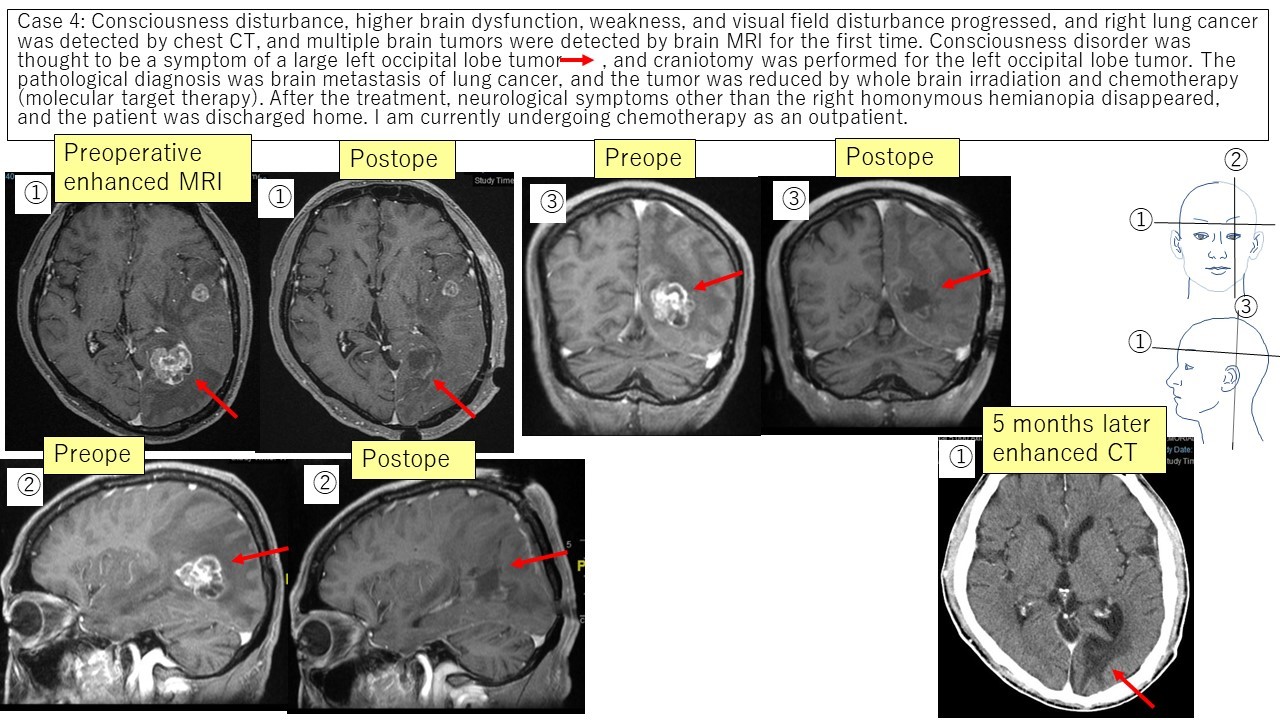

③ Metastatic brain tumor Case 3 Case 4

④ Delayed radiation necrosis Case 5